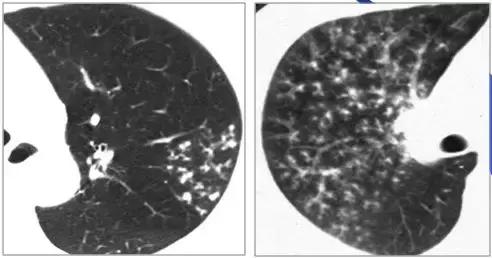

CT征象二:轨道征与印戒征

1、“轨道征”:扩张支气管走行与CT扫描平面平行时

2、“印戒征”:扩张支气管与CT扫描层面垂直时

(正常同级别的肺动脉直径稍大于伴行的支气管内径)

CT表现:在肺野内显示为平行的线样高密度影或环形低密度影伴周围点状高密度影(直径小于前者)

意义:表明有支气管扩张、慢性支气管炎伴发的细支气管扩张等。

柱状支气管扩张(可逆问题)——“轨道征”

慢性支气管炎继发柱状支气管扩张——“轨道征”

柱状支气管扩张与扫描层面垂直——“印戒征”